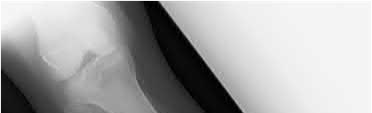

A 38-year-old male suffers the injury shown in Figure A. During operative fixation, free osteoarticular fragments are encountered and reconstruction of these pieces is attempted. Postoperatively, which of the following will have the most beneficial effect on the healing potential of the surviving chondrocytes within these reconstructed articular segments?

Figure A demonstrates a comminuted tibial plateau fracture with significant intra-articular involvement. Basic science evidence has demonstrated that post-operative gentle compressive loading may have a positive impact on articular cartilage healing; however, excessive shear loading may be detrimental.

Irrgang et al provide guidelines for rehabilitation following surgical management of articular cartilage lesions of the knee. They state that after articular cartilage repair, exercises to enhance muscle function must be done in a manner which minimizes shear loading of the joint surfaces in the area of the lesion. The authors also discuss the benefits of gentle compressive loading and motion of the joint, and its positive effects on chondrocyte nutrition.

Furthermore, they recommend a period of protected weight bearing as often being necessary, and that this should be followed by progressive loading of the joint.